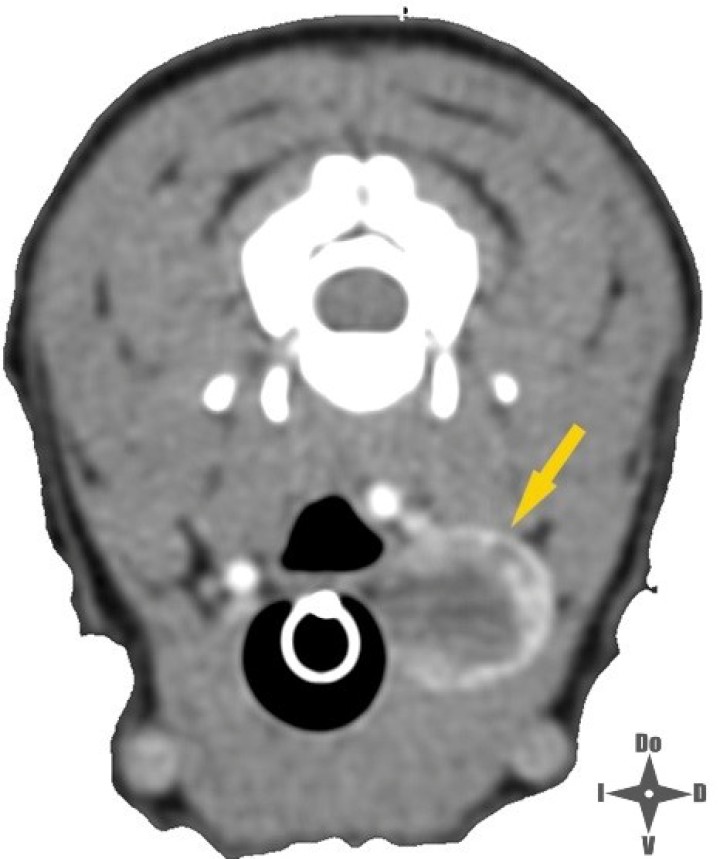

<p>Imagen de TC con contraste IV; la fecha amarilla señala la neoplasia.</p>

Imagen de TC con contraste IV; la fecha amarilla señala la neoplasia.

Las neoplasias tiroideas representan aproximadamente entre el 1,2 y el 3,8 % de las neoplasias caninas,[ Liptak JM: Canine thyroid carcinoma. Clin Tech Small Anim Pract. 2007; 22(2): 75-81. [pubMed] ] siendo los carcinomas más comunes que los adenomas. Los carcinomas tiroideos se caracterizan por su rápido crecimiento y es probable su invasión a tejidos adyacentes como laringe, tráquea, arteria carótida o vena yugular, entre otras estructuras, lo cual es parte de la pesquisa previa para establecer el estadío de la neoplasia.[ Prastiti E, Tzenetidou Z, Papazoglou, LG: Canine thyroid tumours: diagnosis and treatment. Hellenic Journal of Companion Animal Medicine 2018; 7(2): 8-27. ] En el presente caso se realizó previamente una tomografía computarizada (TC) en la que se observó que el tamaño de la neoplasia era de 1,6 x 1,5 x 2,5 centímetros. Seguidamente, se inyectó contraste intravenoso para evaluar el comportamiento invasivo de la neoplasia, no observándose invasión aparente hacia los tejidos adyacentes como tampoco signos de metástasis pulmonar.